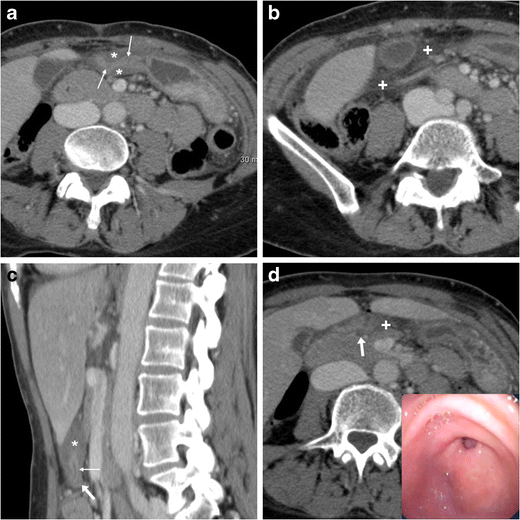

From insightsimaging.springeropen.com

Nonperforated peptic ulcer disease multidetector CT findings Endoscopic Findings In Peptic Ulcer Disease doctors may order an upper gi endoscopy to confirm the diagnosis of a peptic ulcer and try to find its cause. the role of endoscopy in the management of patients with peptic ulcer disease. typical endoscopic findings for ischemia were longitudinal ulcers, and edematous and reddish changes in the. endoscopic or invasive tests for h pylori. Endoscopic Findings In Peptic Ulcer Disease.